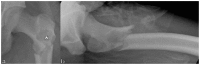

Less than 10% of chondrosarcomas occur in children. In addition, as little as 0.5% of low-grade chondrosarcomas arise secondarily from benign chondroid lesions. The presence of focal pain is often used to crudely distinguish a chondrosarcoma (which is usually managed with wide surgical excision), from a benign chondroid lesion (which can be followed by clinical exams and imaging surveillance). Given the difficulty of localizing pain in the pediatric population, initial radiology findings and short-interval follow-up, both imaging and clinical, are critical to accurately differentiate a chondrosarcoma from a benign chondroid lesion. To our knowledge, no case in the literature discusses a chondrosarcoma possibly arising secondarily from an enchondroma in a pediatric patient. We present a clinicopathologic and radiology review of conventional chondrosarcomas. We also attempt to further the understanding of how to manage a chondroid lesion in the pediatric patient with only vague or bilateral complaints of pain.